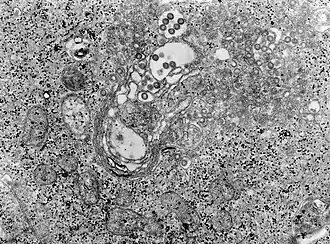

Rift Valley: Фотография ткани под микроскопом инфицированной вирусом лихорадки | |